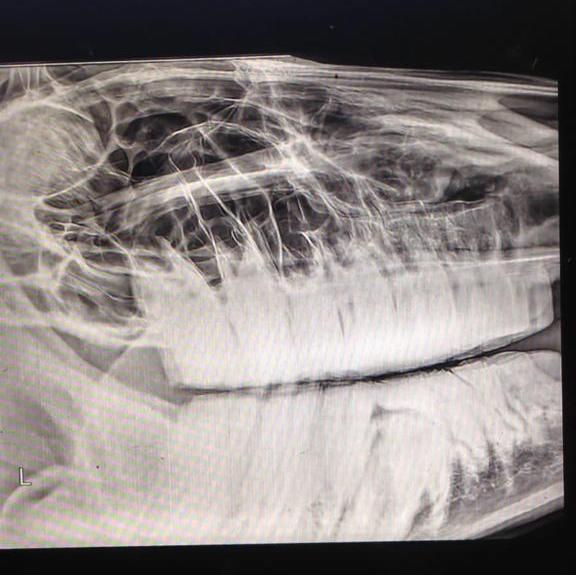

- Orthopädische Untersuchung

- Röntgenologisch und Ultrasonographisch